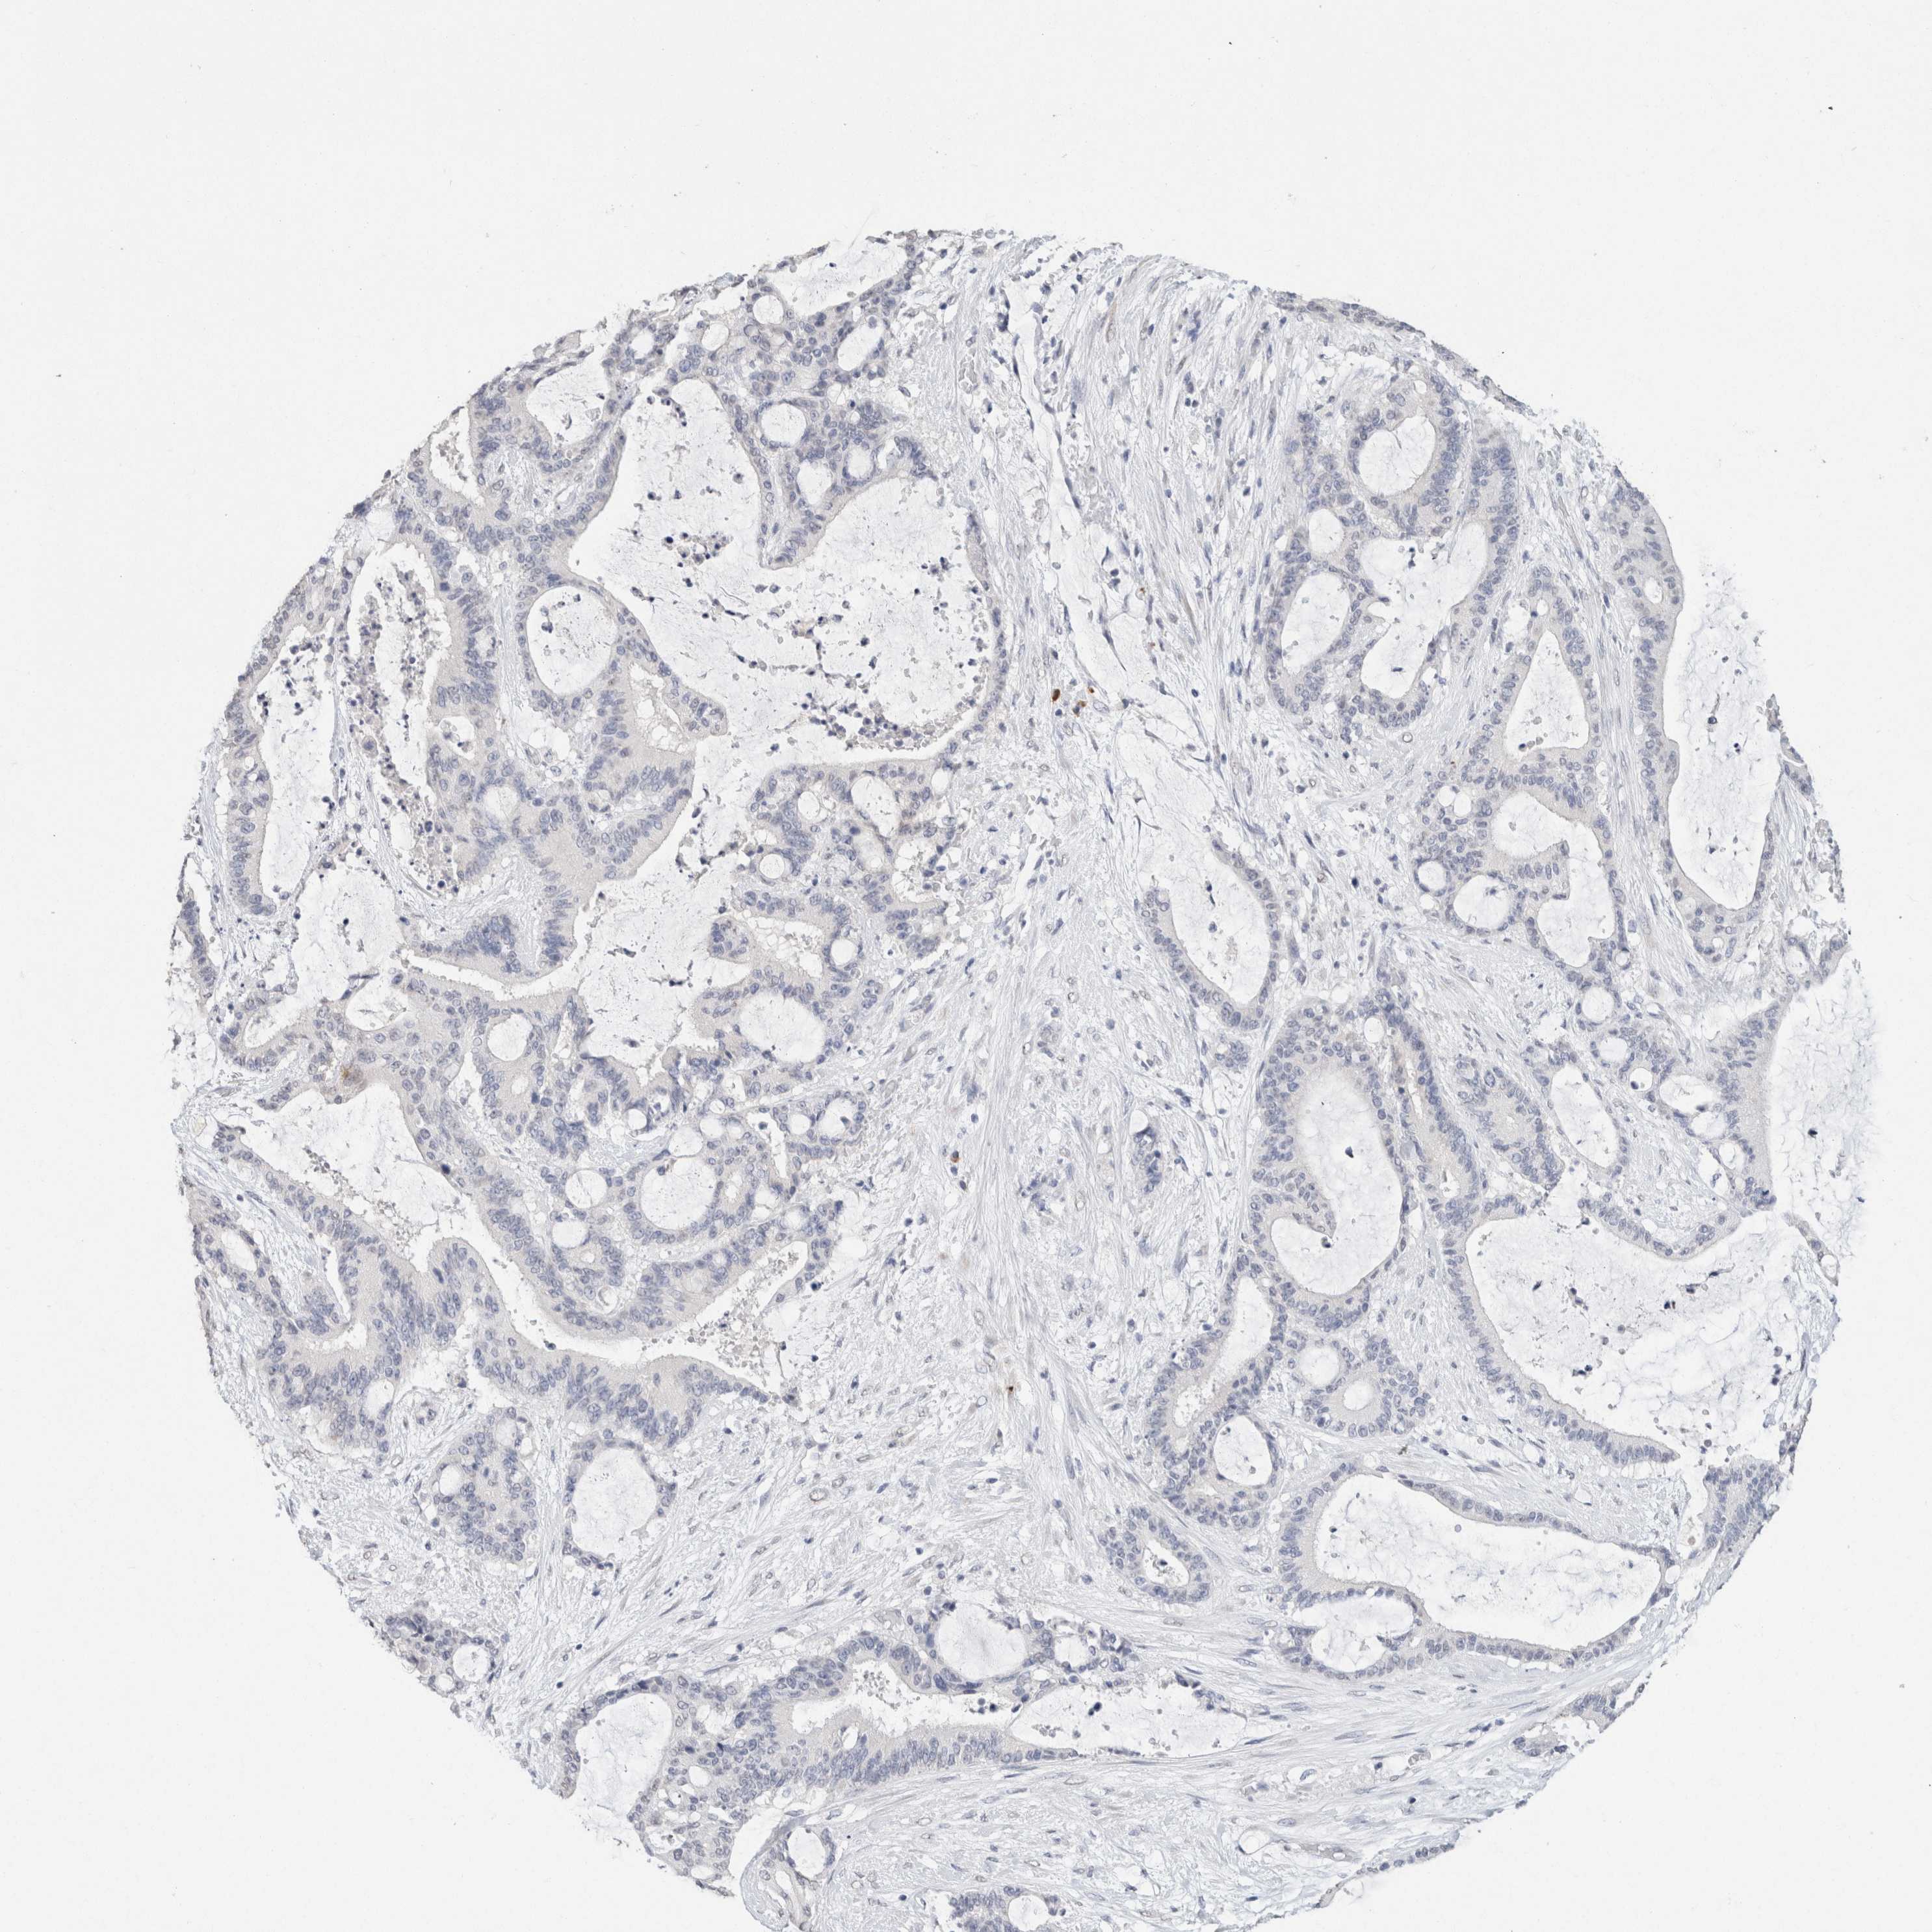

LIVER CANCER - Protein expressioni

A mouse-over function shows sample information and annotation data. Click on an image to view it in a full screen mode. Samples can be filtered based on level of antibody staining by selecting one or several of the following categories: high, medium, low and not detected. The assay and annotation is described here.

Note that samples used for immunohistochemistry by the Human Protein Atlas do not correspond to samples in the TCGA dataset.

Antibody stainingi

Antibody staining in the annotated cell types in the current human tissue is reported as not detected, low, medium, or high, based on conventional immunohistochemistry profiling in selected tissues. This score is based on the combination of the staining intensity and fraction of stained cells.

Each image is clickable and will lead to virtual microscopy that enables deeper exploration of all samples and also displays staining intensity scores, fraction scores and subcellular localization as well as patient and tissue information for each sample.

Antibody HPA050092

Antibody CAB025368

Carcinoma, Hepatocellular, NOS

Cholangiocarcinoma